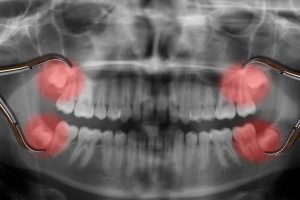

[caption id="attachment_7504" align="alignleft" width="380"]

20 lik diş röntgeni[/caption]

20lik dişler alt ve üst çene arkında en son süren büyük azı dişleridir. Yirmilik dişler her çenede sağda ve solda 2 tane toplamda 4 tanedir.